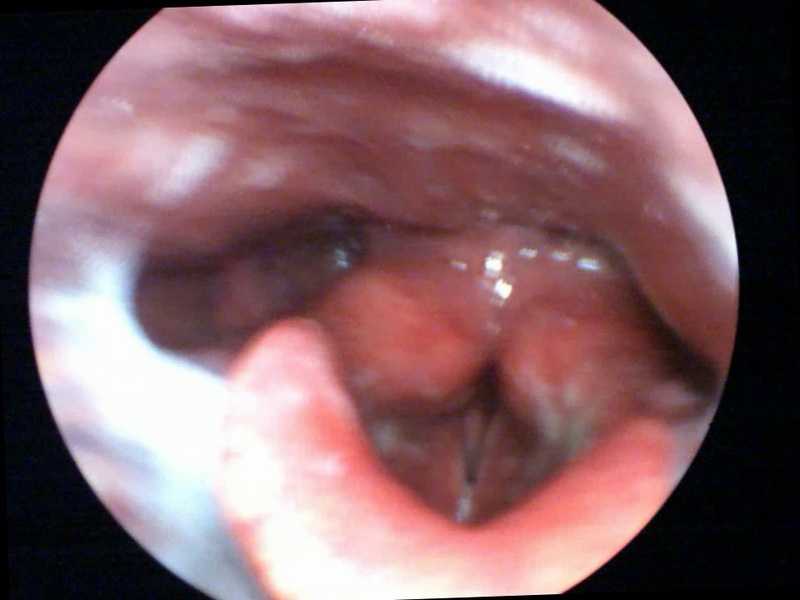

For example, in Photo A we see the specific strategy that we can use in laryngitis, an organic inflammation:

This strategy works in isolation, but also improves outcomes of other therapies in order to achieve a rapid resolution of the problem [8], because the brain reverts to recreate the best homeostasis that it knows.

In laryngitis, the induction of endogenous production of cortisol leads to an improvement in inflammation and edema, the action on the cervical sympathetic plexus improves local vascularisation, and the other points of the strategy accelerate healing, which is observed in laryngostroboscopy, as shown in Photos A1 (before the treatment) and A2 (after the treatment).